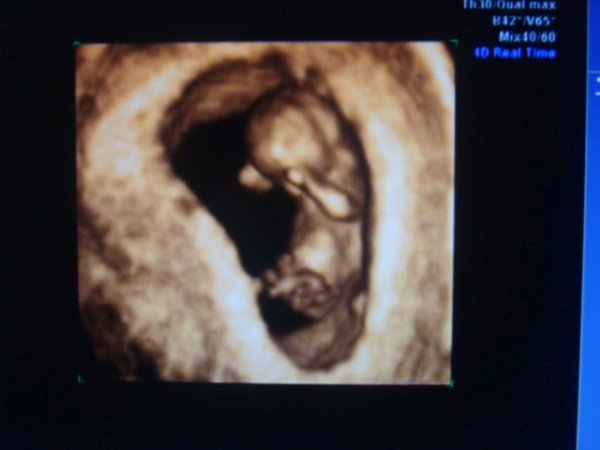

Bemutatom a mi kis babánkat/AKI SPONTÁN BABA/: Kép manó

ime az igért kép Noni babáról